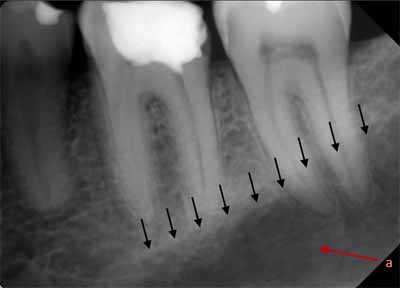

下顎の外側部に向かって後方に移動すると、犬歯、小臼歯、大臼歯が見えます。小臼歯と大臼歯の下には下顎管があり、薄いエックス線不透過性の境界に囲まれた幅広いエックス線透過性の線として現れます。下顎管は下顎の頬側表面にあるオトガイ孔に開口しています。口腔内画像では、オトガイ孔は小臼歯の根尖のすぐ下またはその高さにある丸いエックス線透過性の構造として確認できます(画像 18 および 19 を参照) 。下顎管は下顎枝にあるオトガイ孔から下顎孔まで下顎の外側部分全体に沿って走っています。多くの場合、臼歯の根尖のすぐ下か、同じ高さに位置します。等角投影と軸測投影の両方で、臼歯の頂点に重なって描かれることもあります(画像20と21を参照)。

オトガイ孔の画像では、下顎骨の基底部が見えることも珍しくありません。これは下顎の下縁を形成する、強いエックス線不透過性の線として現れます (画像20と21を比較)。

下顎の水平部分から垂直部分(枝)への移行部には、歯列弓の周囲の頬側に強固な骨の縁があります(画像22を参照)。この骨の縁は斜線と呼ばれ、X線では下顎第三大臼歯の歯冠上を走り、第二大臼歯の上を前方に続く透明なエックス線不透過性の線として確認できます(画像23を参照)。

下顎の臼歯部の舌側には、別の骨の隆起である顎舌骨筋線があります。これは口底筋の付着部も形成し、大部分が大臼歯の根の上にエックス線不透過性の水平線として現れます(画像24を参照)。顎舌骨筋線の太さは個人によって異なるため、X線画像では明瞭に見えたり見えなかったりする場合があります。顎舌骨筋線のすぐ下には、境界が不明瞭なエックス線透過性の領域があります。これは下顎の舌側表面にあるくぼみ、顎下窩です(画像24参照)。